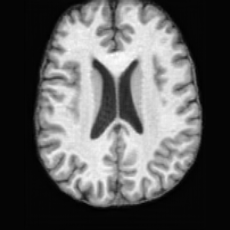

PathologicalHealthyDifferencew/o ACGw/ ACG(a)Refer to captionRefer to captionRefer to captionRefer to captionRefer to captionHealthyPathologicalDifferencew/o ACGw/ ACG(b)Refer to captionRefer to captionRefer to captionRefer to captionRefer to caption

Figure 6: Ablation study of Anatomy Consistency Guidance (ACG): (a) pathology-to-healthy; (b) healthy-to-pathology. Without ACG, edits cause anatomical inconsistencies outside lesions (arrows), whereas ACG keeps modifications lesion-focused.

Anomaly Consistency Guidance. Fig. 6 demonstrates the effectiveness of the proposed Anatomy Consistency Guidance (ACG) on bidirectional editing. Without ACG, the generated brains exhibit noticeable and unrealistic anatomical deformations in non-lesion regions (arrow-indicated), leading to structural inconsistencies between the edited and original brains, as shown in the corresponding difference maps. After incorporating ACG, the model effectively constrains editable modifications within pathological regions, while preserving the remaining anatomy. Tab. 4 further reports their quantitative performances: removing ACG leads to a substantial degradation in all L1, PSNR, and SSIM scores, reaffirming the critical role of ACG in achieving more accurate and structurally consistent reconstructions.